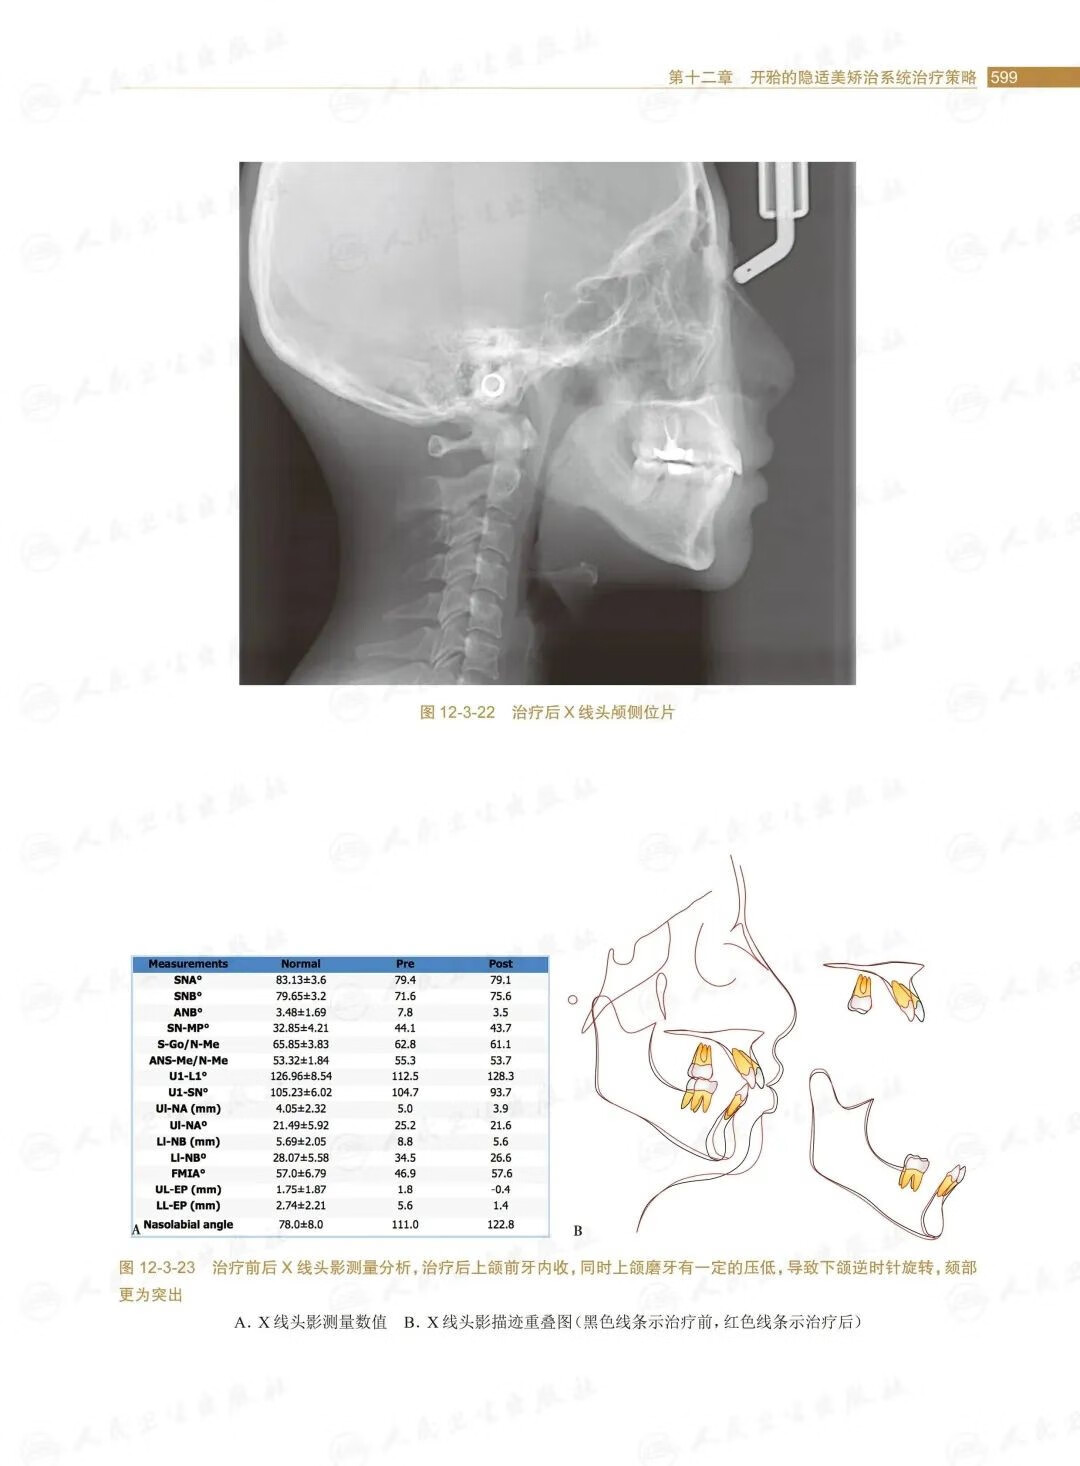

第三節安氏Ⅱ類開的矯治策略/588

第四節安氏Ⅲ類開的矯治策略/601